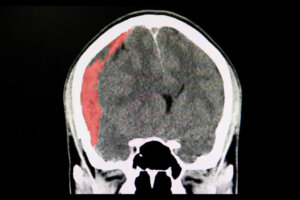

Por outro lado, o derrame hemorrágico ocorre quando um vaso sanguíneo se rompe e sangra dentro do cérebro. Minutos após a ruptura do vaso, as células cerebrais começam a morrer, pois são cercadas por fluido sanguíneo que interrompe seus processos fisiológicos.

É muito difícil distinguir um AVC isquêmico de um hemorrágico com base nos sintomas. Portanto, em todos os casos é necessária uma visita ao pronto-socorro, onde serão realizados exames como tomografia axial computadorizada, arteriografia e ressonância magnética.